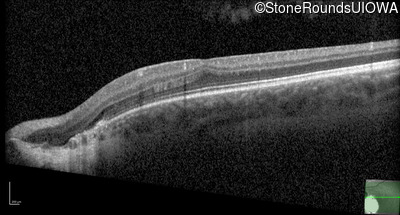

Optical Coherence Tomography - Left - 20/50 +2

Exemplar / OCT Stack

OCT Stack